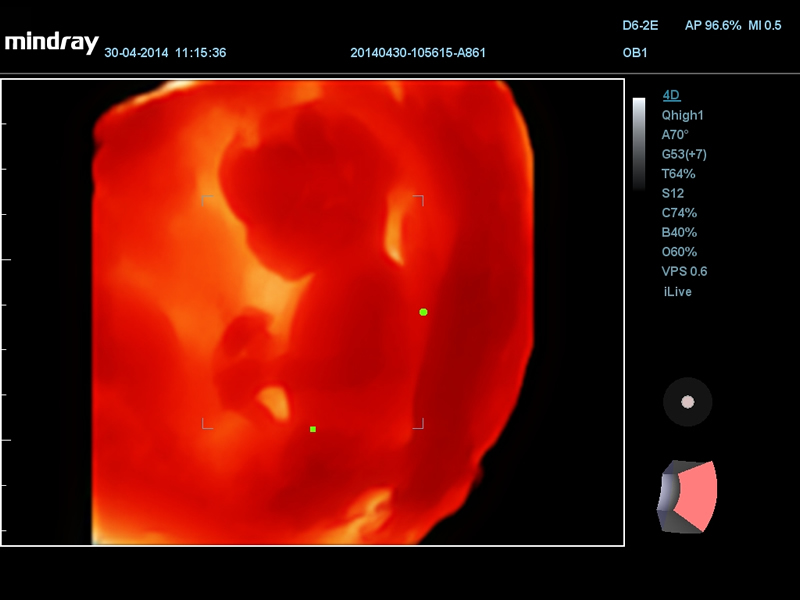

14-недельный эмбрион с i Live

Пупочные артерии